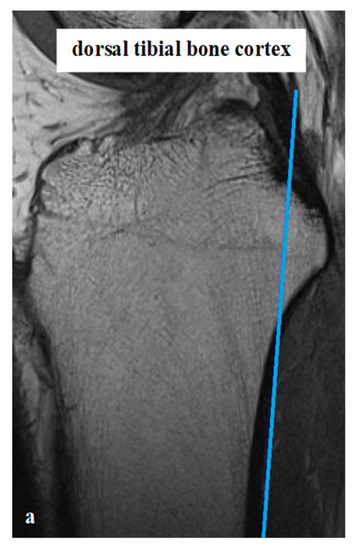

All measurements were taken via the PACS system (Picture Archiving and Communication System). Software from GE Healthcare called CentricityTM Universal Viewer was used (RA1000, edition 2019, Buckinghamshire, Great Britain). The osteoarthritis score of each knee joint was classified according to Kellgren/Lawrence (KL), in order to group patients as KJH or KJD. The TS was measured on the medial and lateral knee-joint surface according to Karimi et al. (TSKmed and TSKlat) [37] and Hudek et al. (TSHmed and TSHlat) [38]. As a reference for determining the inclination of the tibial plateau, Karimi et al. described the dorsal tibial bone cortex and Hudek et al. the tibial-shaft axis. Figure 1 and Figure 2 show the principle of the measurement methodology.

Figure 1.

Exemplary depiction of the measurements of the tibial slope according to Karimi et al. [37] for medial (TSKmed, (b)) and lateral (TSKlat, (c)) knee-joint surface: The measurements of TSK were performed in sagittal view of the knee joint in MRIs. To determine the right position of the dorsal tibial bone cortex for each TSKmed and TSKlat, a reference line was set in the best available image (a). Based on this reference line, the dorsal inclination angle of the tibial plateau was determined in the medial (TSKmed, (b)) and lateral (TSKlat, (c)) joint sections.